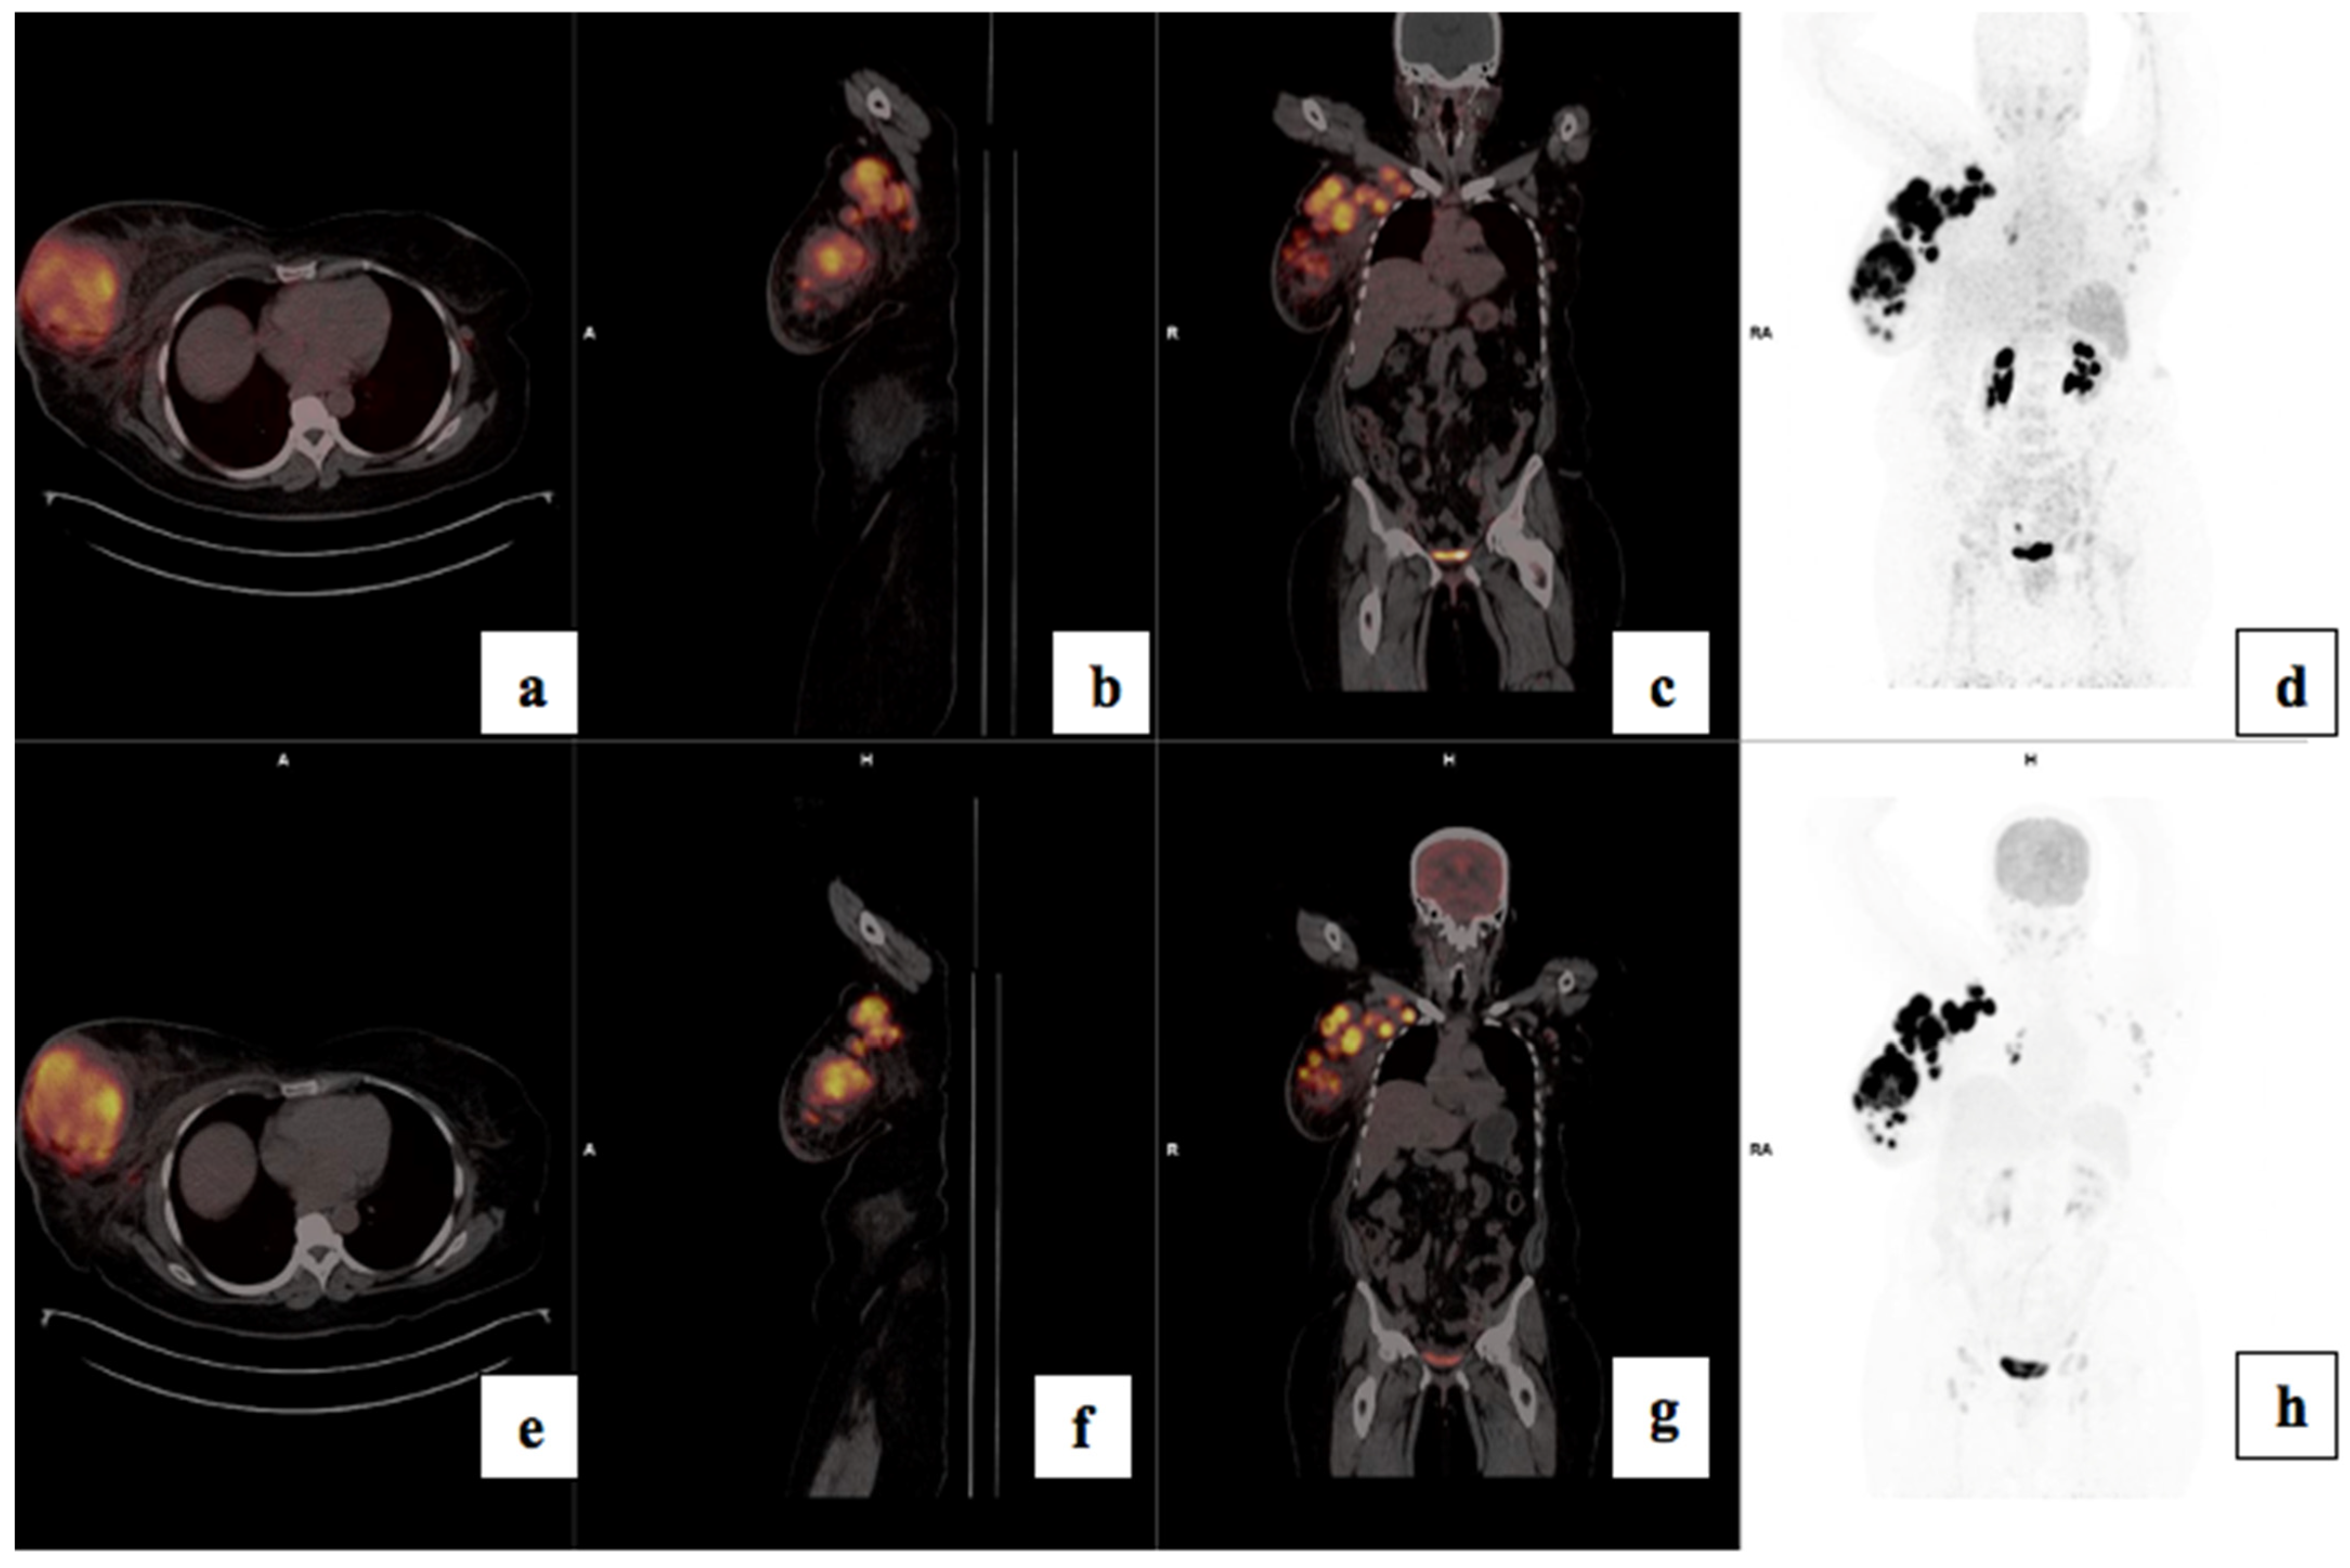

3.4. Visual Analysis

3.5. Treatment Response